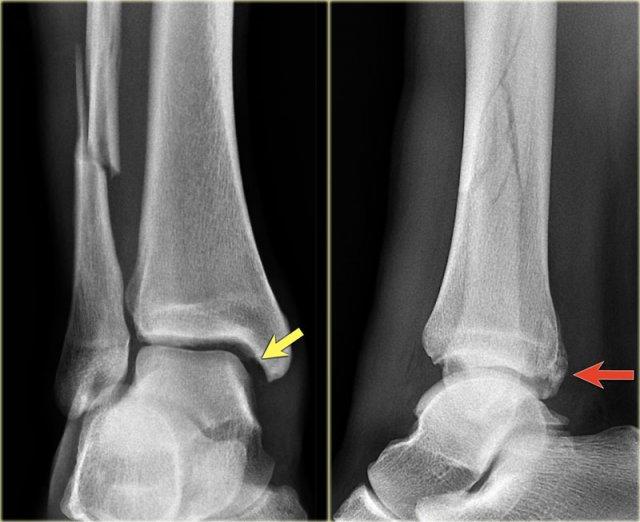

Hình ảnh X-quang cho thấy một gãy xương Weber B điển hình.

Hãy quan sát kỹ hình ảnh trước rồi tiếp tục đọc.

Bạn có nhận ra đây là giai đoạn nào không?

Đây là tổn thương Weber B giai đoạn 4.

Lưu ý rằng cả 4 giai đoạn đều có thể nhìn thấy:

- Đứt dây chằng chày mác trước – biểu hiện bằng sự giãn rộng khoảng cách giữa đầu xa xương chày và xương mác (khoảng sáng bên ngoài).

- Gãy xương mác chéo ở mức khớp chày mác – tức là gãy kiểu Weber B.

- Gãy xương Tertius – thấy trên phim thẳng (mũi tên đỏ) và trên phim nghiêng (mũi tên vàng).

- Rupture của dây chằng bên trong – được thấy như sự mở rộng của khoảng cách giữa mắt cá chân trong và xương sên (khoảng sáng trong)